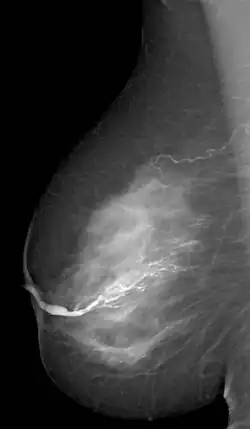

La galactographie (du grec ancien γαλακτος / galactos, lait et γραφειν / graphein, écrire) est un examen radiologique complémentaire du sein qui permet de visualiser les canaux galactophores.

Il se pratique en injectant un produit de contraste iodé hydrosoluble dans un canal galactophore, puis en réalisant des clichés lors d'une mammographie.

Cet examen permet de mettre en évidence une anomalie à l'intérieur des canaux notamment des images lacunaires, des végétations papillaires intracanalaires multiples pathologiques (tumeur bénigne, papillome)[1].